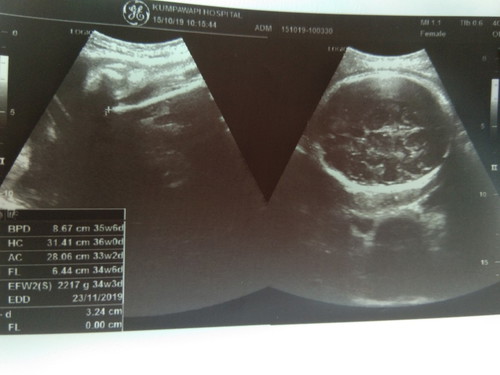

33w 2217gแล้ว ?

ผมกลับหัวรอแล้วนะ...แต่อิแม่ยังไม่ซักเสื้อผ้าหนูเลย ???????ทีมพฤศจิกายน นน.ตัวเล็กเท่าไรกันแล้วค่ะ บ้านนี้ท้อง2แล้วยังตื่นเต้นเหมือนเดิม???

บ้านนี้เพิ่งซักเสร็จเมื่อวานเลยจร้า เหนื่อยมากๆ เตรียมหิ้ว ลูกชายกลับหัวรอแล้วจร้า 35+5วีค